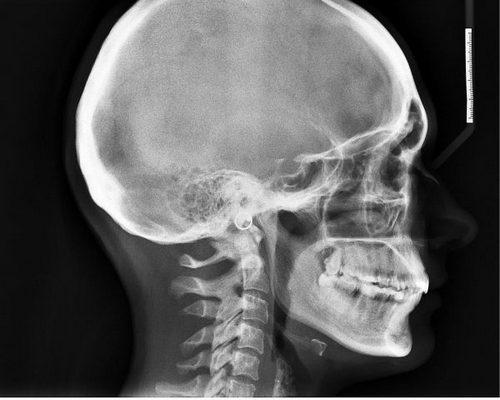

Поэтому однозначно ответить на вопрос: почему, когда встаешь, болит голова – может только врач после проведенного обследования. Показывают состояние мозга способы нейровизуализации, ультразвуковые манипуляции и другие варианты проверки:

- компьютерная ренгеновская томография: наиболее точный метод диагностирования патологий органов и систем в человеческом теле. Сегодня КТ часто применяют для установления каких-либо отклонений в работе головного мозга. Методика, во-первых, безопасна, а во-вторых, очень точна. С ее помощью обнаруживаются опухоли и другие новообразования в черепе, устанавливаются любые проблемы с кровообращением в церебральных сосудах или угнетением ЦНС. После процедуры врач получает четкое изображение костей, мозговых оболочек и артерий.

Для проведения КТ требуется специальный аппаратам – томограф. Процедура проходит либо с введением контрастного вещества, либо без него, анестезия при этом не требуется. Пациент находится в положении лежа на спине или на боку. Человек все время обследования должен лежать неподвижно, нельзя садиться или подниматься. Именно по этой причине КТ не всегда рекомендуют для маленьких детей или людей с психическими отклонениями. Таким категориям КТ делают под наркозом;

- магнитно-резонансная томография: альтернатива КТ, когда рентген противопоказан. Наиболее часто к МРТ прибегают, чтобы установить локализация и размеры новообразований в черепе, проверить состояние мозга до и после операции, понять, отчего у человека возникают приступы головной боли, обмороки. МРТ фактически дает врачу полное представление о состоянии всех мозговых структур;